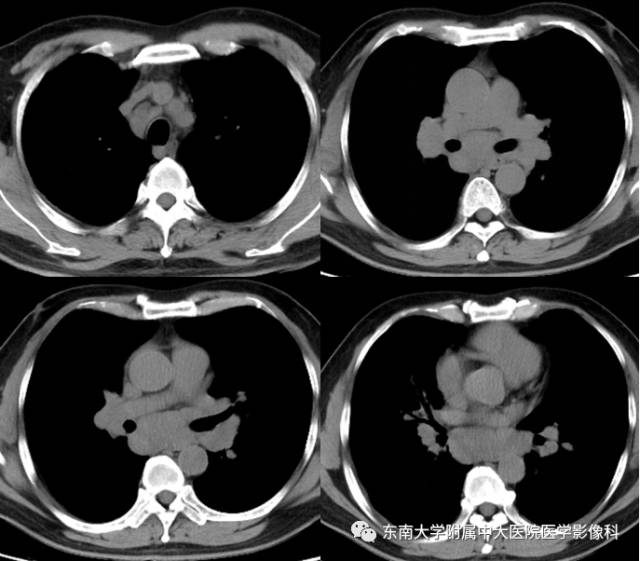

结节病1例CT

男,43岁,因“咳嗽咳痰1月余,加重1天”入院。

CT